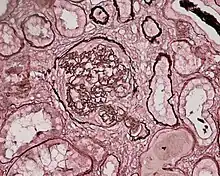

| Photomicrograph of a kidney biopsy from a person with crescentic glomerulonephritis showing prominent fibrocellular crescent formation and moderate mesangial proliferation in a glomerulus. Hematoxylin and eosin stain. | |

Rapidly progressive glomerulonephritis

Rapidly progressive glomerulonephritis, also known as crescentic GN, is characterised by a rapid, progressive deterioration in kidney function. People with rapidly progressive glomerulonephritis may present with a nephritic syndrome. In management, steroid therapy is sometimes used, although the prognosis remains poor.[9] Three main subtypes are recognised:[4]: 557–558

Histopathologically, the majority of glomeruli present "crescents". Formation of crescents is initiated by passage of fibrin into the Bowman space as a result of increased permeability of glomerular basement membrane. Fibrin stimulates the proliferation of endothelial cells of Bowman capsule, and an influx of monocytes. Rapid growing and fibrosis of crescents compresses the capillary loops and decreases the Bowman space, which leads to kidney failure within weeks or months.